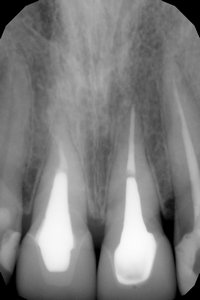

Вы чувствуете дискомфорт в верхнем 6-ом зубе, так как в нем есть воспалительный процесс. По данному рентгеновскому снимку (хронический апикальный периодонтит). Зуб следует перелечить. Проконсультируйтесь очно со стоматологом-терапевтом.